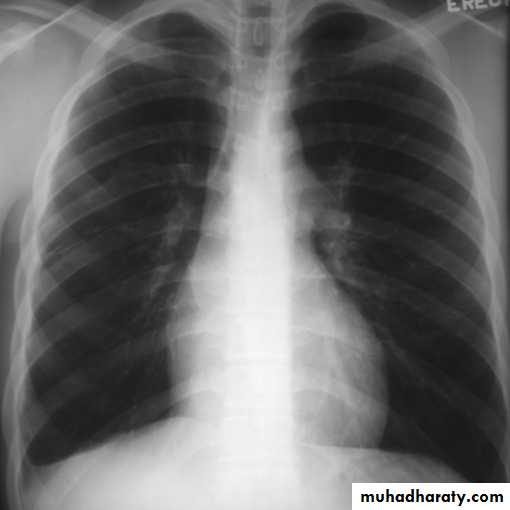

The pleura :

• Pleural effusion : collection of fluid within the pleural space. This can be further divided into Transudate , exudate, according to protein content .Other type of fluid collection within pleural space are

• Chest x-rays are the most commonly used examination to assess for presence of a pleural effusion, however it should be noted that on a routine erect frontal chest x-ray as much as 200-500 ml of fluid is

• required before it becomes evident .

blunting of the costophrenic angle

blunting of the cardiophrenic angle

fluid within the horizontal or oblique fissures

eventually a meniscus will be seen, on frontal films seen laterally and gently sloping medially

with large volume effusions, mediastinal shift occurs away from the effusion

• Lateral films are able to identify a smaller amount of fluid ( about75%)as the costophrenic angles are deepest posteriorly posteriorly

Pleura effusion signs

Obliteration of costo-pherinic anglesMeniscus sign

Lenticular sign